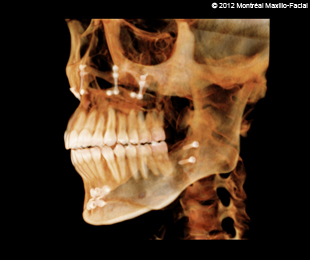

- 13 FÉVRIER 2012 - Rendez-vous avec mon chirurgien pour mes mâchoires

- 20 MARS 2012 - Je vais probablement m'en sortir sans broches!

- Photos & radiographies